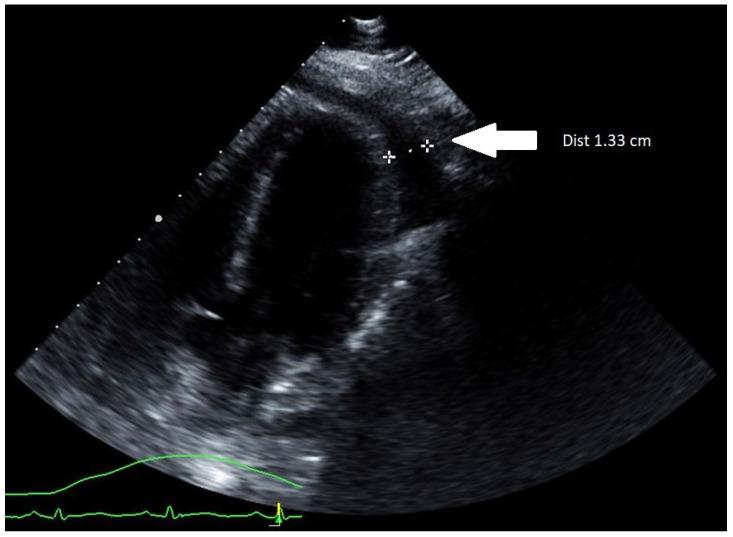

Myocarditis is an infrequent complication of influenza infection that is most often diagnosed clinically in the setting of confirmed influenza infection and elevated cardiac enzymes. Pericarditis can also occur in cases of influenza myocarditis and may require pericardiocentesis for tamponade. Patients with fulminant myocarditis have cardiogenic shock; however, echocardiographic findings may be subtle, showing a preserved ejection fraction and diffuse left ventricular wall thickening (compared to baseline) due to inflammatory edema. Recognizing these echocardiographic findings in the appropriate clinical setting facilitates the early recognition of fulminant myocarditis. Therefore, we report a case of fulminant influenza A myocarditis in healthy 37-year-old women complicated by transient left ventricular wall thickening and tamponade, highlighting the importance of early diagnosis and supportive management for a successful outcome.

心肌炎是流感感染的一种罕见并发症,通常在确诊流感感染且心肌酶升高的情况下通过临床诊断。心包炎也可能发生在流感心肌炎病例中,可能需要心包穿刺引流以缓解心包填塞。暴发性心肌炎患者会出现心源性休克;然而,超声心动图表现可能不明显,显示射血分数正常,且由于炎症性水肿导致左心室壁弥漫性增厚(与基线相比)。在适当的临床环境中识别这些超声心动图表现有助于早期识别暴发性心肌炎。因此,我们报告一例37岁健康女性患甲型流感暴发性心肌炎,并发短暂性左心室壁增厚和心包填塞,强调早期诊断和支持性治疗对于成功治疗的重要性。